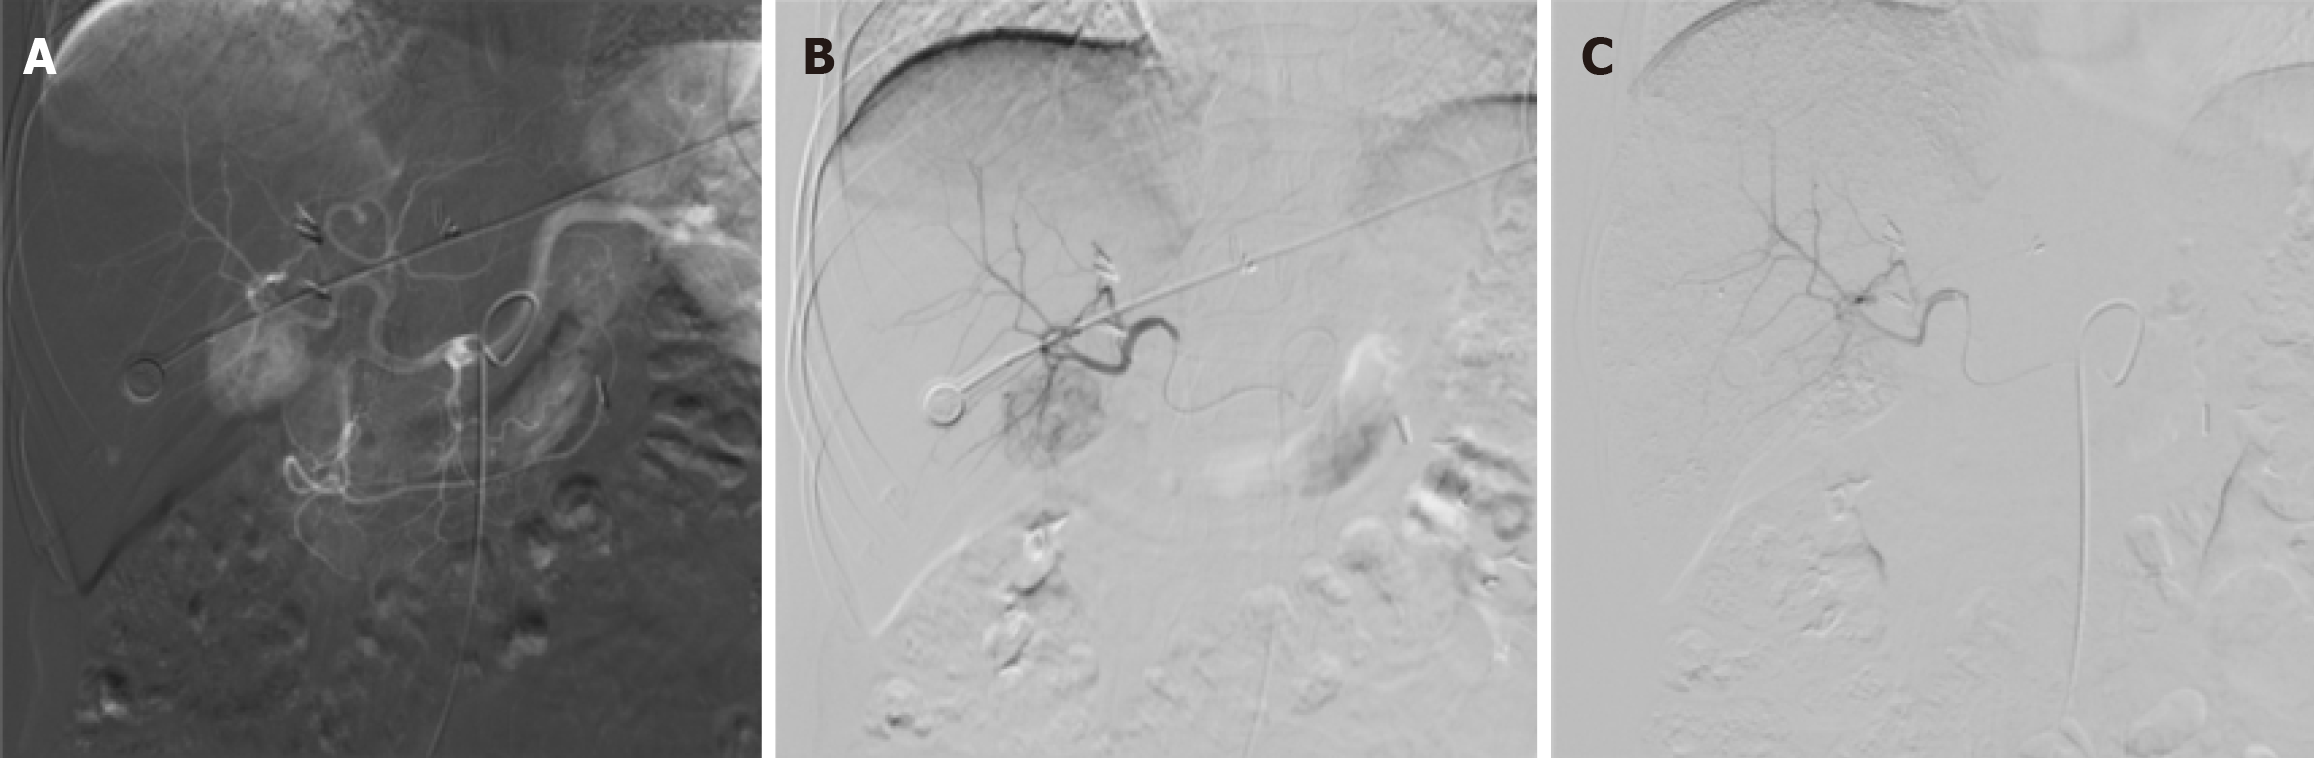

Following a multidisciplinary team discussion, transarterial embolization (TAE) was selected as the treatment strategy for the HEAML located in the right lobe. Under local infiltration anesthesia with 2% lidocaine, the right femoral artery was accessed using the Seldinger technique, and a standard arterial sheath was introduced. Angiography of the superior mesenteric artery and celiac trunk was performed using a 5F RH catheter, revealing satisfactory portal venous return but significant tumor vascularity and staining in the liver parenchyma. A microcatheter was advanced to achieve superselective catheterization of the tumor-feeding artery, through which 8 mL of lipiodol was administered. Post-embolization angiography demonstrated complete resolution of tumor staining, indicating successful embolization of the tumor vasculature (Figure 4). The patient tolerated the procedure well, with no intraoperative or postoperative discomfort or complications observed.